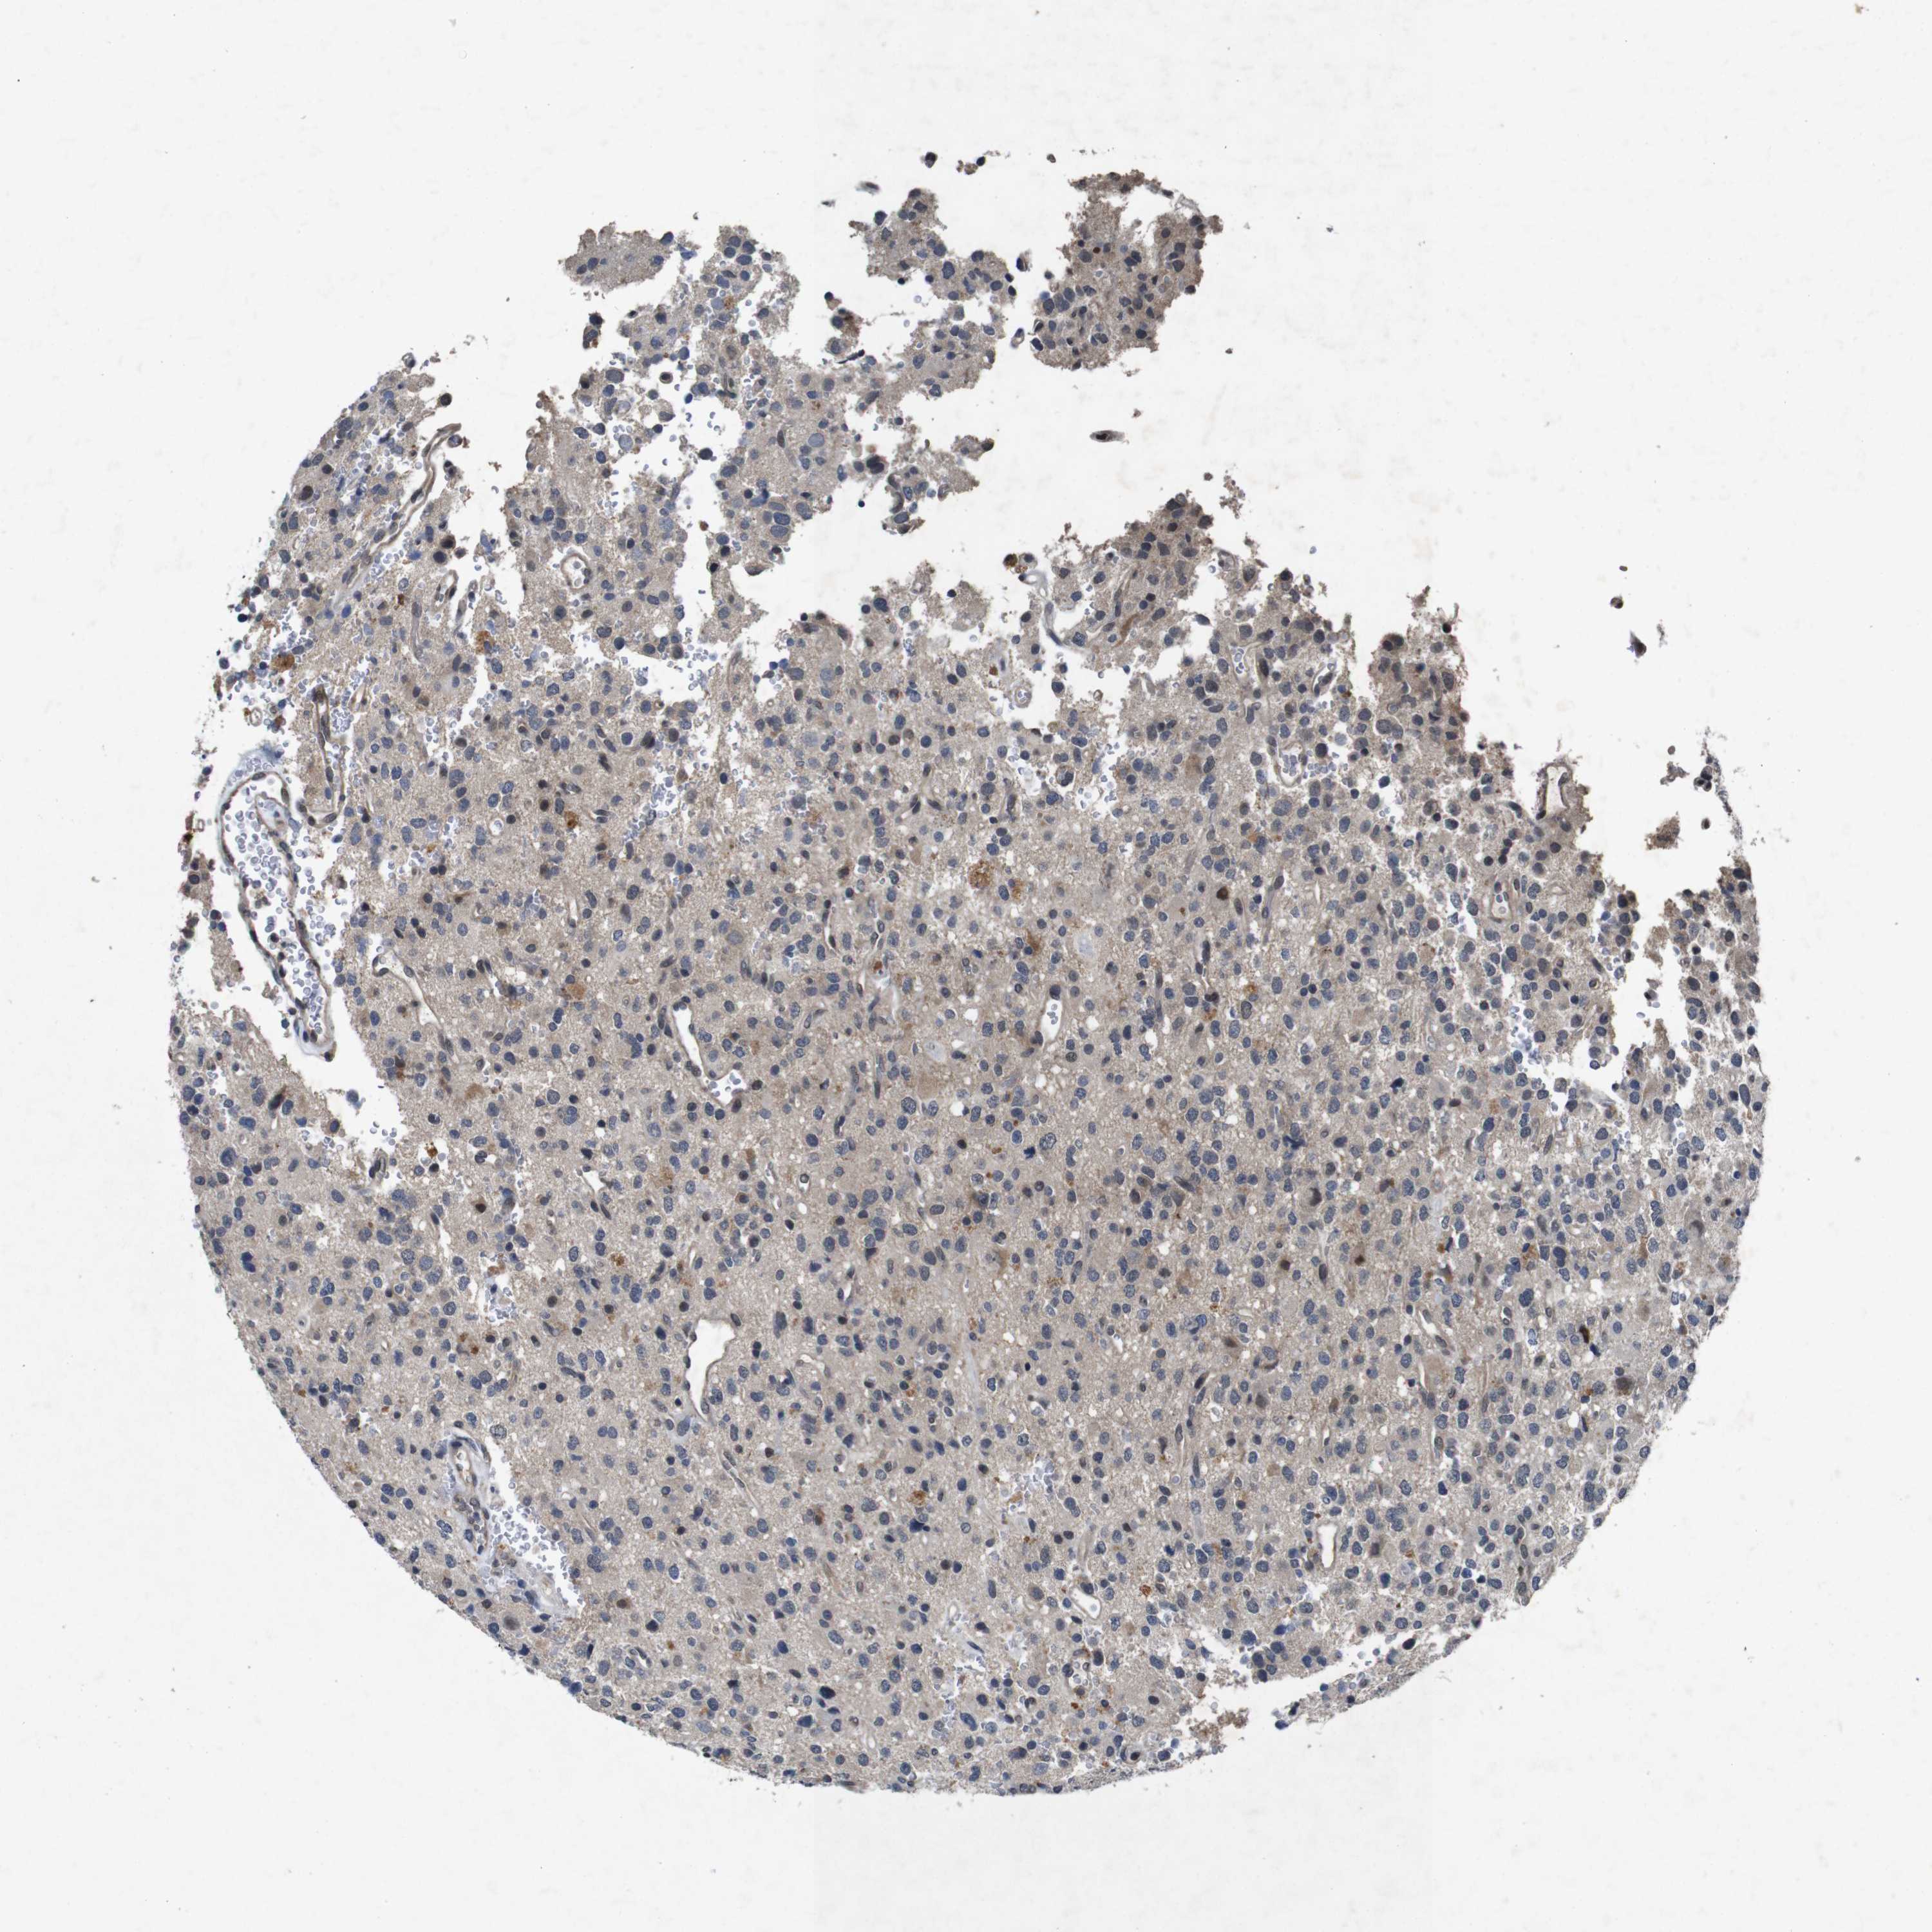

GLIOMA - Protein expressioni

A mouse-over function shows sample information and annotation data. Click on an image to view it in a full screen mode. Samples can be filtered based on level of antibody staining by selecting one or several of the following categories: high, medium, low and not detected. The assay and annotation is described here.

Note that samples used for immunohistochemistry by the Human Protein Atlas do not correspond to samples in the TCGA dataset.

Antibody stainingi

Antibody staining in the annotated cell types in the current human tissue is reported as not detected, low, medium, or high, based on conventional immunohistochemistry profiling in selected tissues. This score is based on the combination of the staining intensity and fraction of stained cells.

Each image is clickable and will lead to virtual microscopy that enables deeper exploration of all samples and also displays staining intensity scores, fraction scores and subcellular localization as well as patient and tissue information for each sample.

Antibody HPA026441

Antibody CAB013090

Staining

High

Medium

Low

Not detected

Intensity

Strong

Moderate

Weak

Negative

Quantity

>75%

75%-25%

<25%

None

Location

Nuclear

Cytoplasmic/membranous

Cytoplasmic/membranous,nuclear

Glioma, malignant, High grade

Glioma, malignant, Low grade